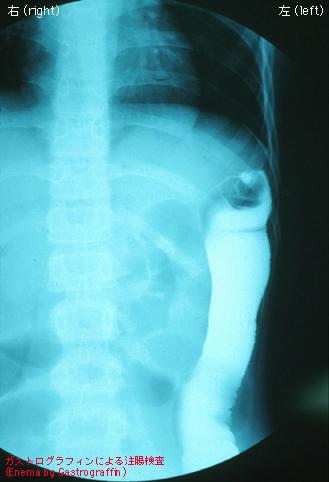

유년성 횡행결장암의 일례 (증례제시:국립병원 나가사키 의료센터)

[Image-ID:2958]

질환(병리주체)의 분류

악성 상피성종양/선암

부위(장기별)

대장/횡행

검사방법

X-P

종양의 육안분류

2형(궤양국한형)/

종양의 최대경(밀리미터)

30~34

종양의 심달도

ss(a1)